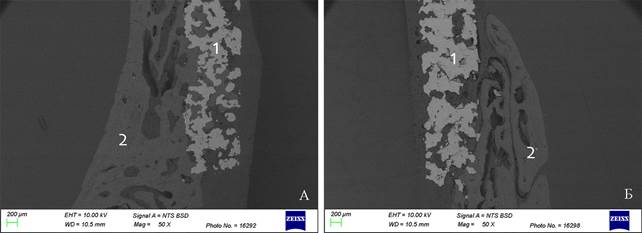

Световая микроскопия не позволяет исследовать препараты, в которых наряду с формирующейся костной тканью, имеется металлический имплантат. При удалении имплантата в процессе изготовления гистологических препаратов частично разрушается формирующаяся костная ткань, и микроскопическая картина не дает полного представления об изучаемой области «имплантат-кость». На микрофотографии на 40 сутки эксперимента при использовании сканирующего электронного микроскопа виден пористый имплантат и формирующаяся костная ткань, прорастающая в поры имплантата (рисунок 9А). Такое прорастание обеспечивает пожизненную стабильность имплантата. Во 2 группе прорастание в пористую структуру не выражено, хотя формирование костной мозоли в виде наплыва на имплантат прослеживается (рисунок 9Б).

Рис. 9. Спил образцов костей крыши черепа кролика с имплантатом: А- 1 группа, Б- 2 группа. 40-е сутки эксперимента: 1 -имплантат, 2 - кость. Сканирующая электронная микроскопия, BSD режим, ускоряющее напряжение 10 кВ. Увеличение *50

Примечание: фотография выполнена авторами в ходе эксперимента.

На большем увеличении при электронной микроскопии можно рассмотреть волокна, плотно контактирующие с имплантатом и прорастающие в поры имплантата (рисунок 10), что свидетельствует о формировании костной ткани и фиксации имплантата.